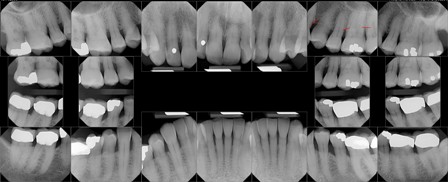

• Your referral slip and a FULL-MOUTH SET OF PERIAPICAL RADIOGRAPHS from your referring dentist.

It is important that every patient have a full mouth set of x-rays so Dr. Baker can to do a complete examination. We can also take your x-rays at an additional fee if you do not have them. If you have a general dentist, we will request your x-rays from them first, if we take a set here, we will send your dentist a copy of your x-rays and a letter explaining your periodontal health and the treatment planned in our office. We use Dexis digital x-rays. These state-of-the-art x-rays provide: